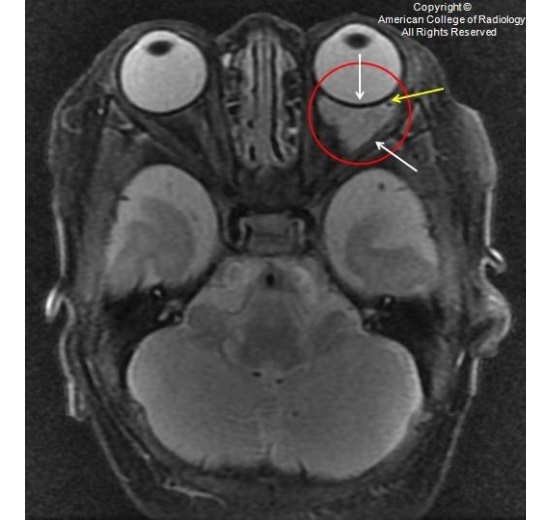

图 1 为 T1,可见一分叶状眶内肿块(红圈),信号与脑实质和肌肉相比表现为等、长 T1。可见临近的蝶骨局部呈扇形改变(黄色箭头)。未侵犯临近骨质,病变和骨质之间可见一条状短 T1 信号

图 6 横断强化 T1,可见肿块累及眶内(红色箭头)及眶外间隙(黄色箭头)。此外,肿块包绕外直肌(红圈),肿块和眶骨见可见一正常条状的组织信号(白色箭头)

IH 典型的影像学表现为:分叶状、边缘光滑、边界清楚的肿块。眶骨受累罕见,但可有临近骨质的膨胀性或扇形改变。MR 可显示 IH 的血管来源性的特征,即病灶周围可见血管流空信号。MRA 可见扩张的供血动脉。增强扫描可见快速、均匀的强化。典型 IH 信号为等、短 T1、长 T2。